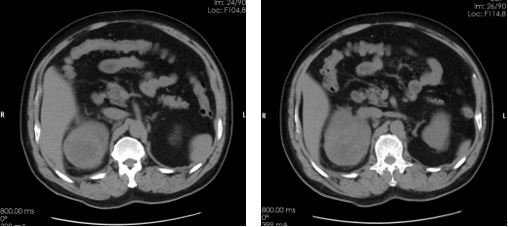

临床资料: 男性,65岁,血尿3天就诊。 扫描方法: 常规GSI平扫+增强,对比剂碘海醇(350mgI/100ml)80ml,3ml/s。 CT印象:

平扫右肾上极低密度肿块影

动脉期肿块明显增强

分泌期及排泄期肿块内对比剂廓清,呈典型快进快出表现